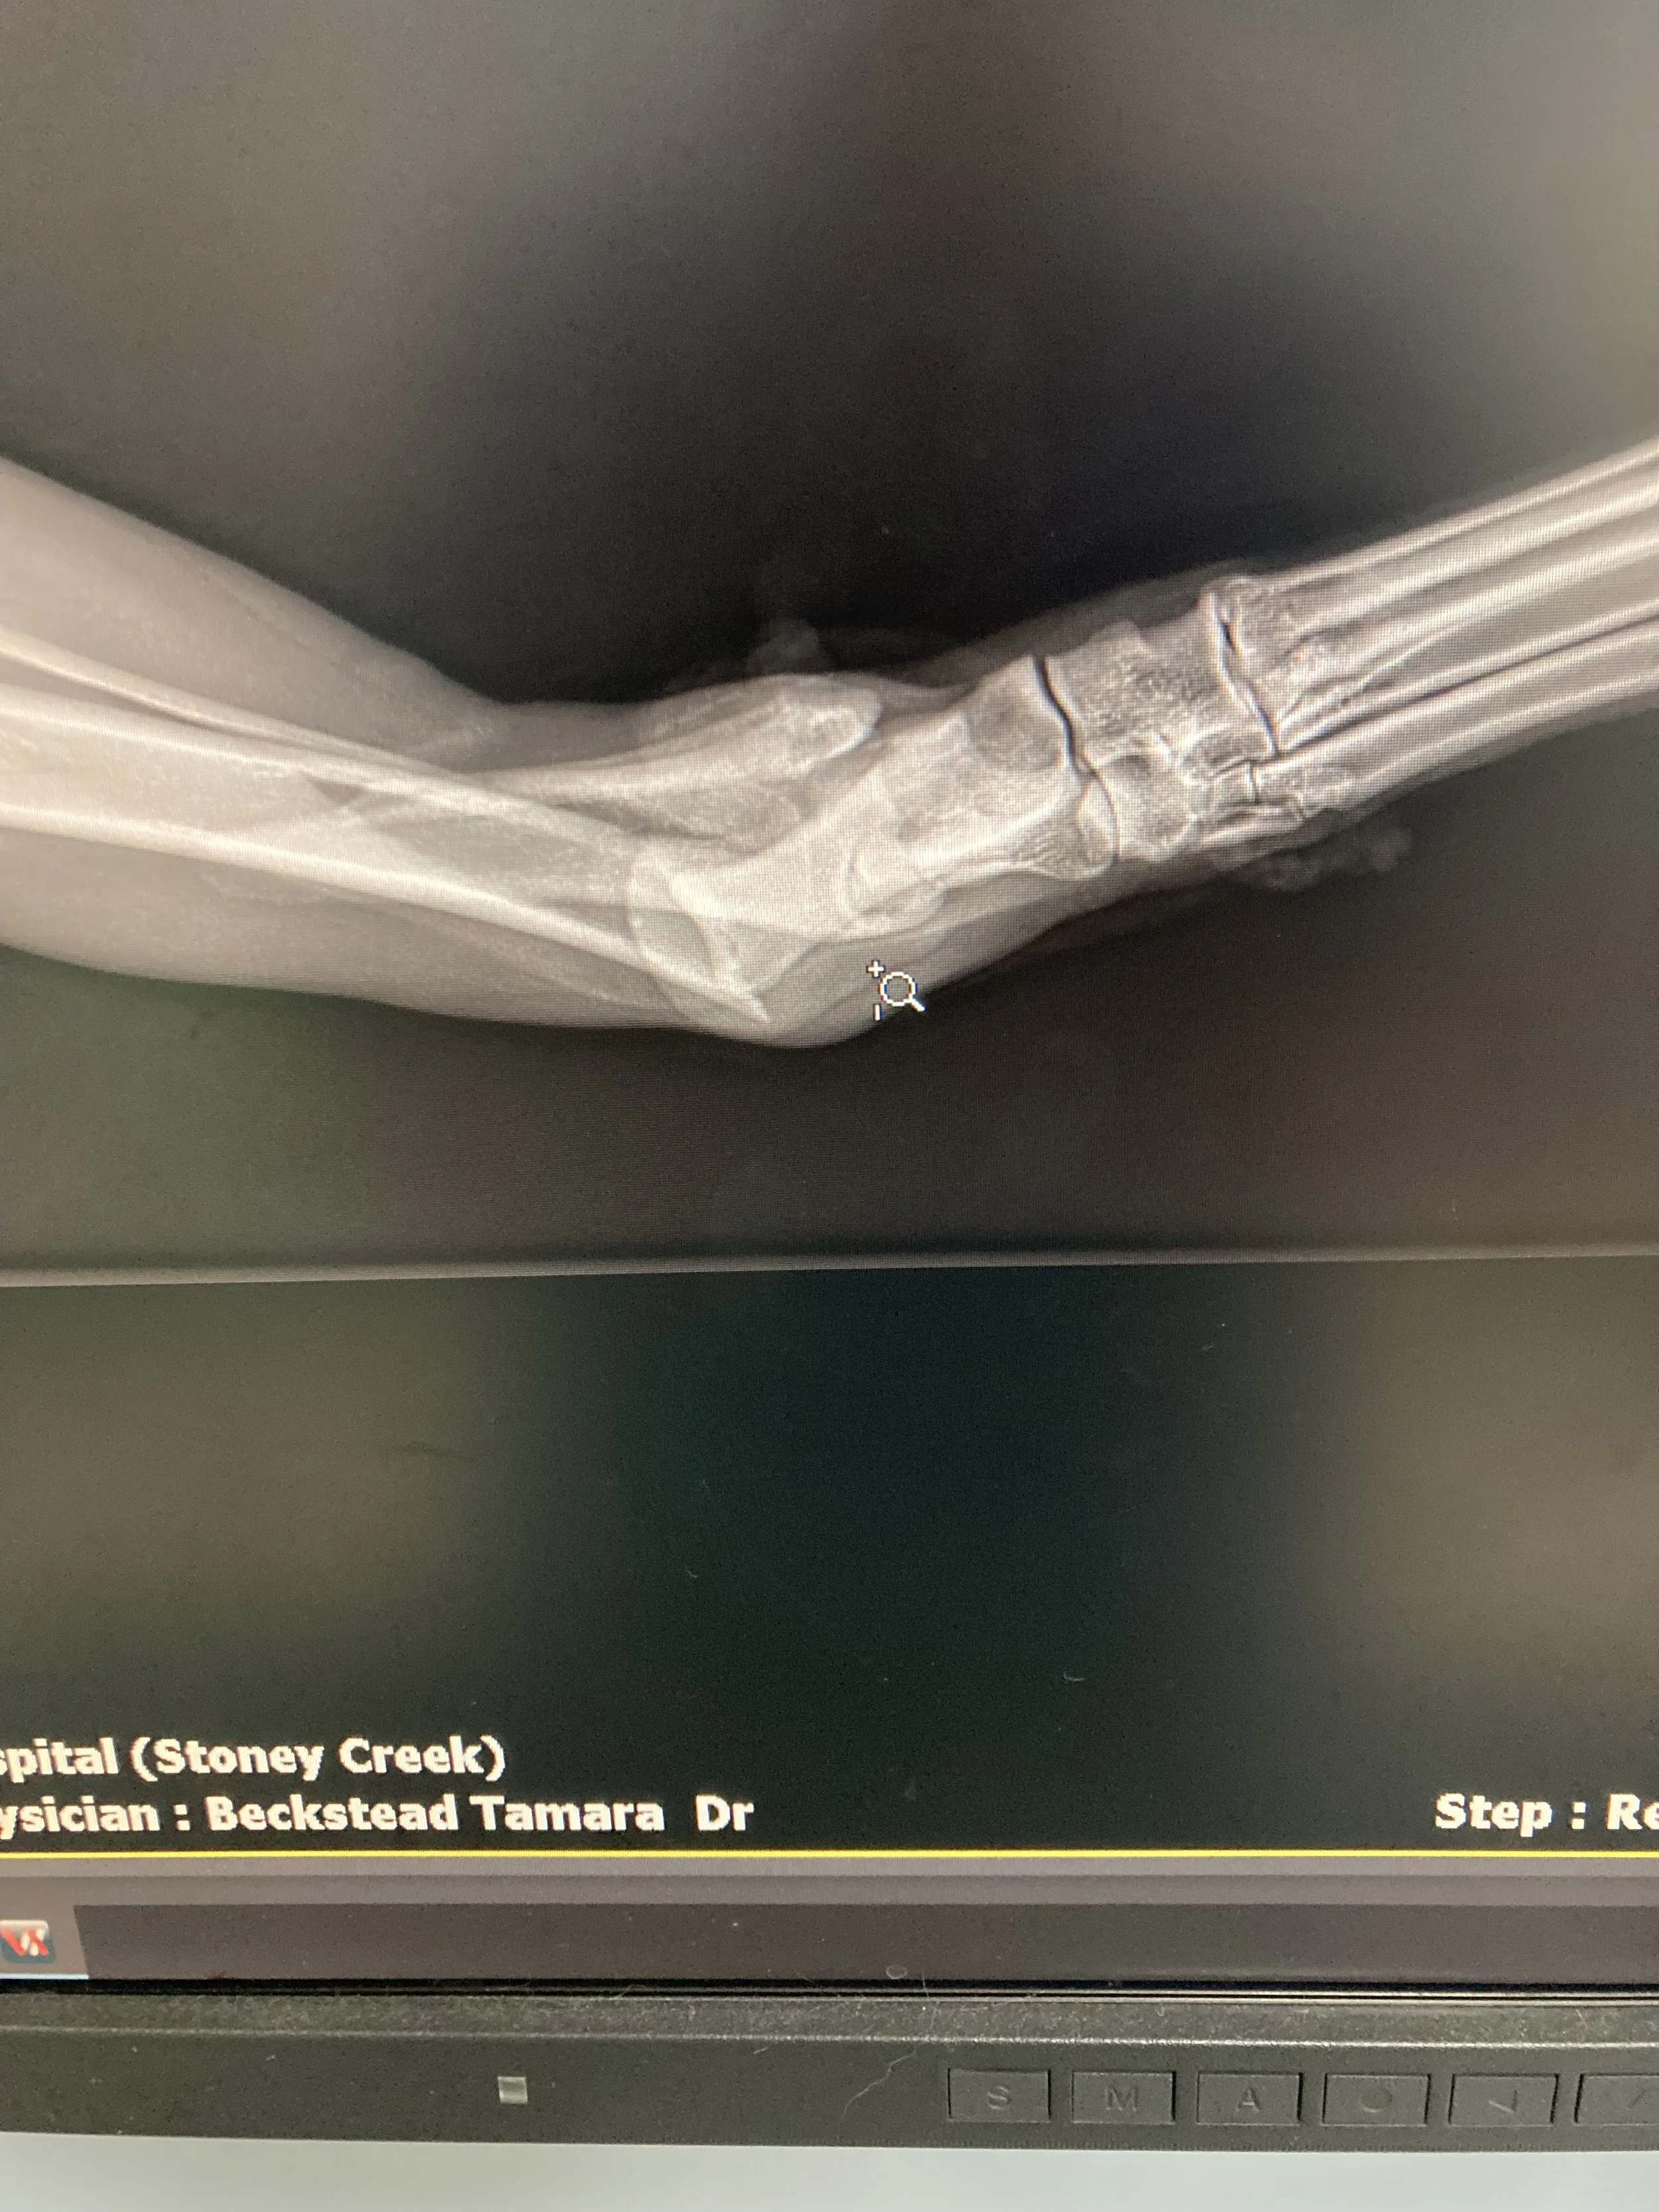

X-ray image showing a fractured forearm with multiple breaks in the radius and ulna bones.